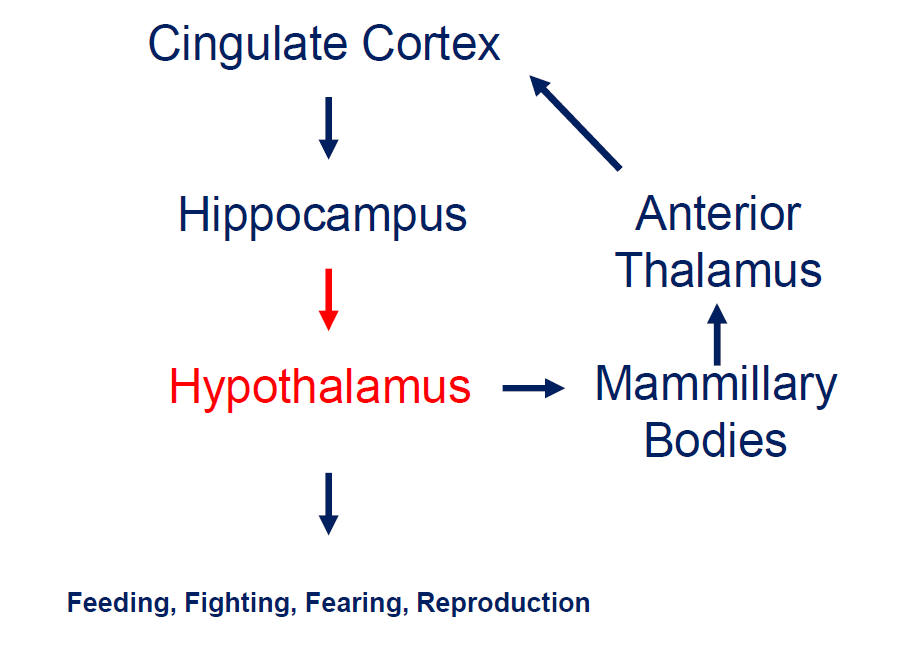

What is the limbic circuit?

Association areas activate the hippocampus, which reverberates in the Papez circuit until information is stored permanently

Hippocampus → fornix → mamillary bodies → anterior thalamic nucleus → cingulate cortex → hypothalamus